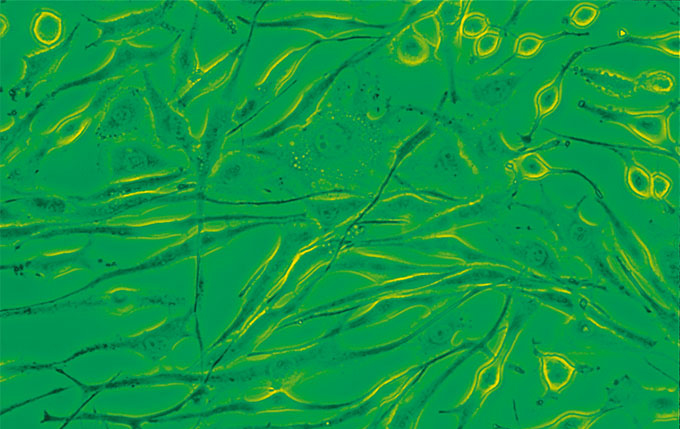

相衬

简易的相衬附件可以在10×、40×和100×下提供高反差的细胞和细菌图像。